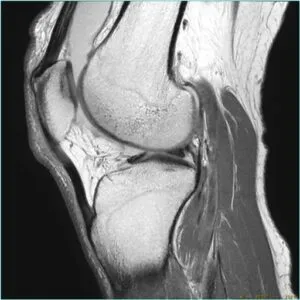

MRI

GE社製のSIGNA Creator 1.5T(テスラ)を導入しています。強力磁石と電波を使って体内の状態を鮮明に見ることができます。膝関節疾患を始めとする他の関節の疾患はもちろん、神経、筋肉・腱の異常や、腫瘍病変などの診断に有用です。

MRIで検査した画像